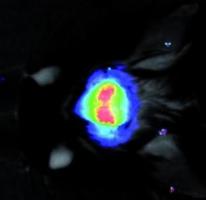

Actualité publiée le 26/07/2016ÉPILEPSIE: Un nouveau GPS cérébral pour guider la chirurgie

Actualité publiée le 09/07/2016